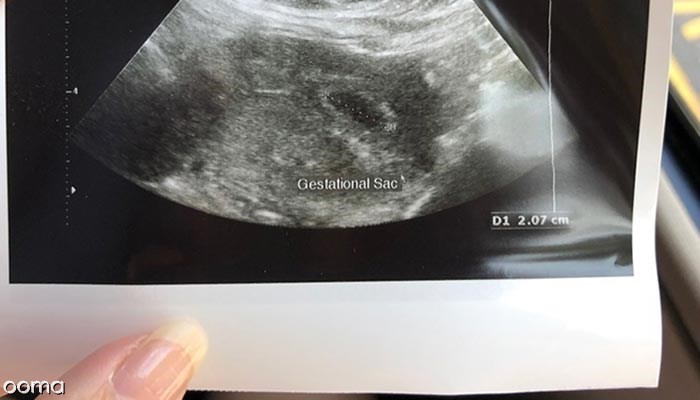

ساک حاملگی یکی از اولین نشانه های بارداری است که می تواند در سونوگرافی واژینال و شکمی دیده شود. این ساک معمولا در سونوگرافی در هفته 5 حاملگی مشاهده می شود اما گاهی اوقات در سونوگرافی در هفته 3 حاملگی نیز قابل مشاهده است. قطر ساک حدود 2 تا 3 میلی متر است و لبه سفید و مرکزی روشن دارد.

درواقع زمانی که سطح هورمون بارداری به 1500 تا 2000 برسد، ساک حاملگی قابل مشاهده می شود. داشتن ساک حاملگی اطلاعات زیادی در مورد سلامتی بارداری شما نمی دهد و مشخص نمی کند که نطفه وجود دارد یا خیر؟ ساک حاملگی اساسا محفظه ای است که جنین را احاطه کرده و حاوی مایع آمنیوتیک است. گام بعدی در سونوگرافی معمولا مشاهده کیسه زرده در داخل ساک حاملگی است.